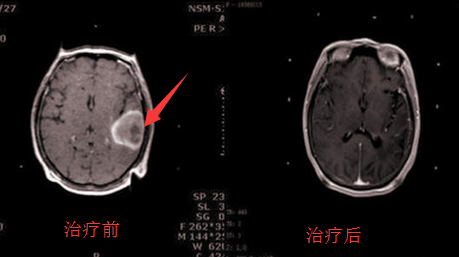

颞叶脑胶质瘤治疗前后对比